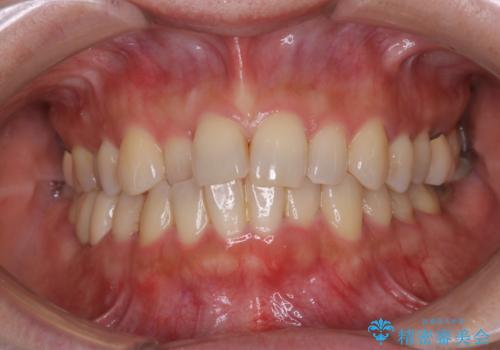

[ マウスピース矯正 ] がたがたした歯並びを治したい

担当医 大元洋佑

![[ マウスピース矯正 ] がたがたした歯並びを治したいの症例 治療前](https://seimitsushinbi.jp/wp/wp-content/uploads/2024/04/IMG_0106-500x350.jpg?v=1711951424)

![[ マウスピース矯正 ] がたがたした歯並びを治したいの症例 治療後](https://seimitsushinbi.jp/wp/wp-content/uploads/2024/04/46939b7482334672d3a091da1562afec-500x350.jpg?v=1711951403)